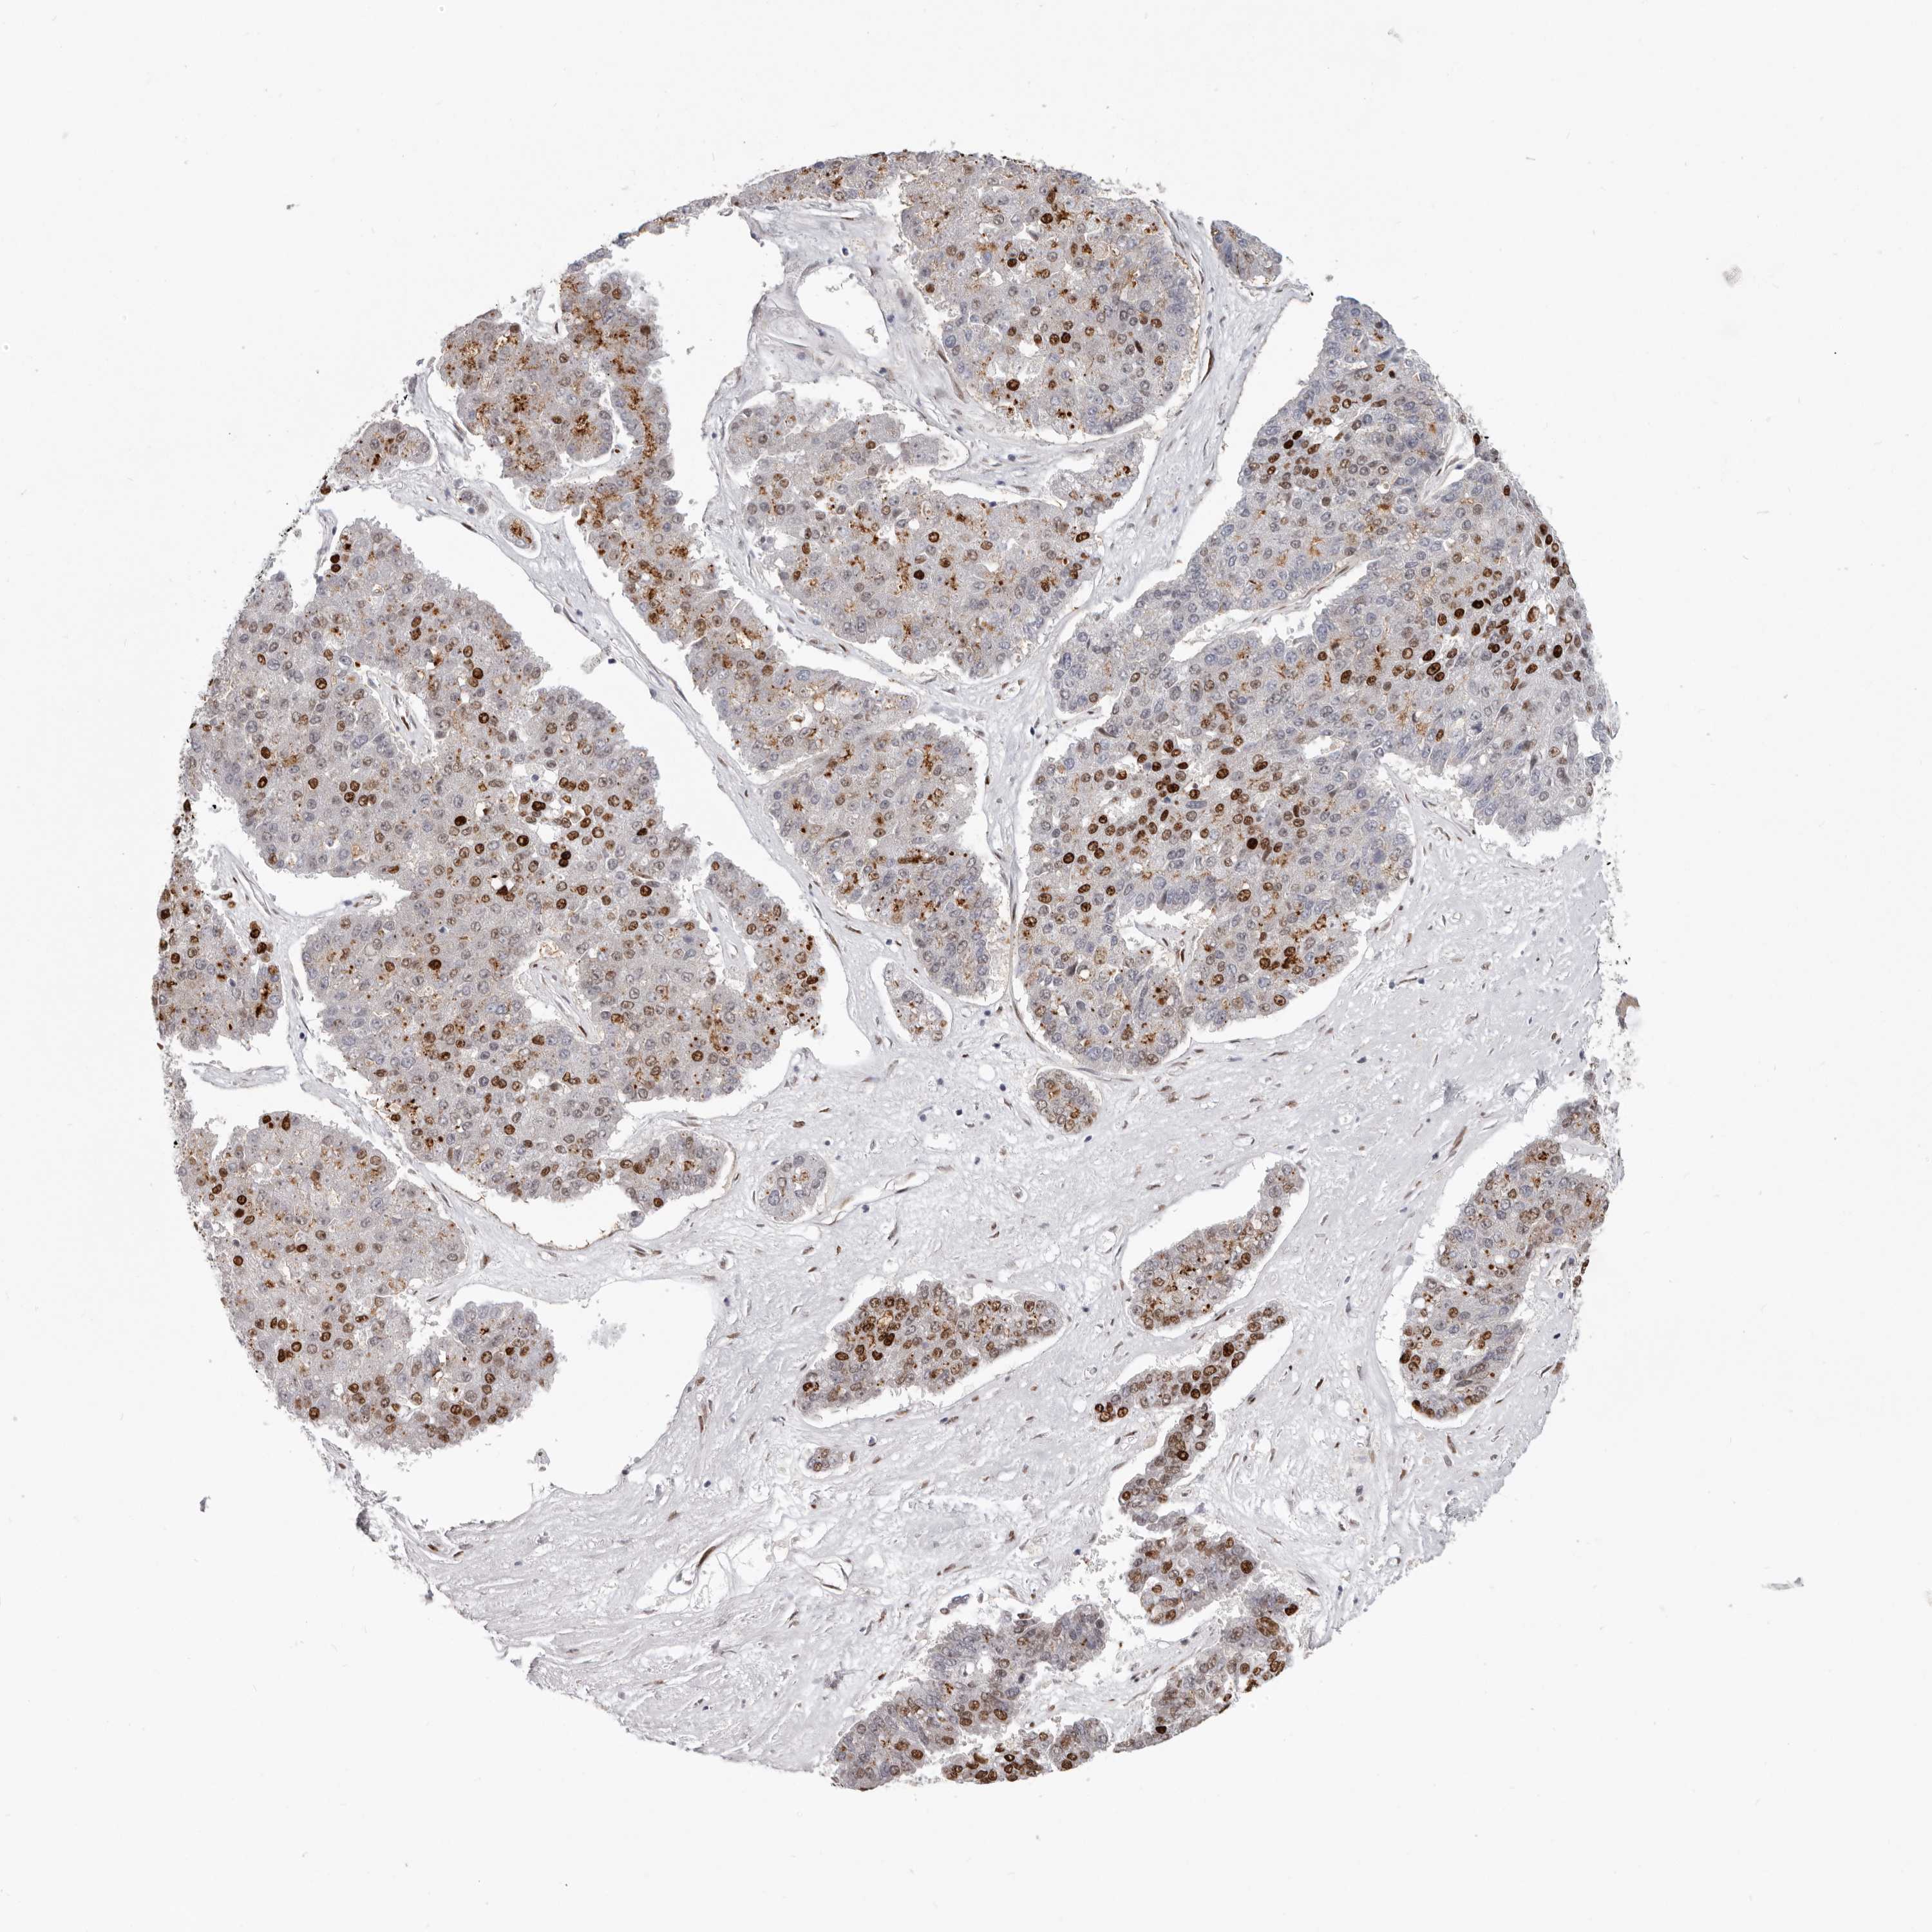

PANCREATIC CANCER - Protein expressioni

A mouse-over function shows sample information and annotation data. Click on an image to view it in a full screen mode. Samples can be filtered based on level of antibody staining by selecting one or several of the following categories: high, medium, low and not detected. The assay and annotation is described here.

Note that samples used for immunohistochemistry by the Human Protein Atlas do not correspond to samples in the TCGA dataset.

Antibody stainingi

Antibody staining in the annotated cell types in the current human tissue is reported as not detected, low, medium, or high, based on conventional immunohistochemistry profiling in selected tissues. This score is based on the combination of the staining intensity and fraction of stained cells.

Each image is clickable and will lead to virtual microscopy that enables deeper exploration of all samples and also displays staining intensity scores, fraction scores and subcellular localization as well as patient and tissue information for each sample.

Antibody HPA029272

Staining

High

Medium

Low

Not detected

Intensity

Strong

Moderate

Weak

Negative

Quantity

>75%

75%-25%

<25%

None

Location

Nuclear

Cytoplasmic/membranous

Cytoplasmic/membranous,nuclear

Adenocarcinoma, NOS